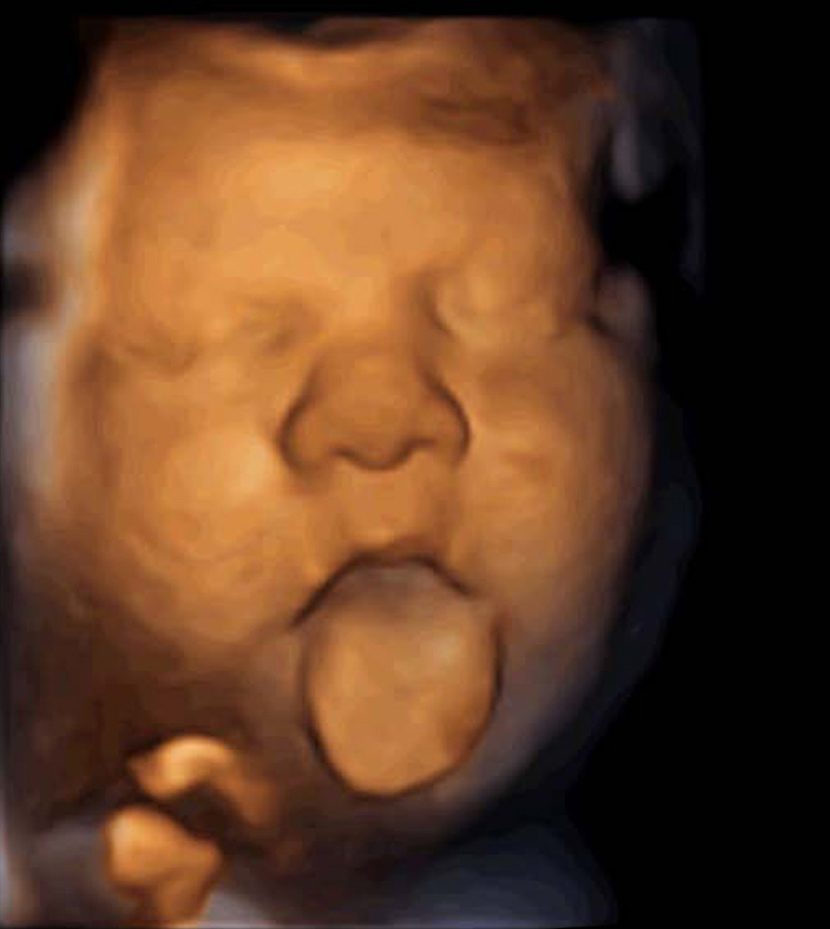

- In the case of music emitted from the vagina, 87% of foetuses move their mouths or tongues and almost half pull out their tongues as far as they will go. They perform vocalisation movements prior to the acquisition of language.

Barcelona, 6 October 2015 - After only 16 weeks of existence, foetuses hear and respond to music as long as it is emitted from their mother’s vagina. Foetuses respond to this stimulus by opening their mouths and pulling their tongues out as far as possible, making vocalisation movements – prior to the acquisition of language.

Using ultrasound scans, the research team compared the reaction of the foetuses and the results were statistically significant. When music was applied from the vagina, 87% of foetuses moved their mouths or tongues and approximately half of them reacted with a very noticeable movement, opening their jaws very wide and pulling out their tongues as far as possible, says Dr. Alex García Faura, the Scientific Director of Institut Marquès and co-author of the article. On applying music emitted through the abdomen or soundwaves, these changes in the expressions of the foetuses were not observed.